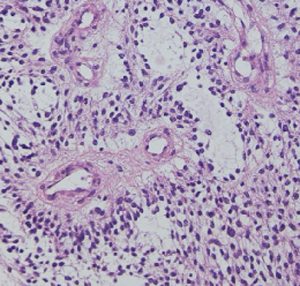

毛様類粘液性星細胞腫の病理像です。関質が広くて粘液用の物質が貯留されています。これは手術で取る時にドロドロの腫瘍に見えますから,ちょっと硬い普通の毛様細胞性星細胞腫とは判別できます。この病理像をもつ腫瘍は,患者さんの年齢が年長児になっていくと,自然に変化して普通の毛様細胞性星細胞腫に変わっていきます。腫瘍も年をとるのだと考えられます。ですから,毛様類粘液性星細胞腫は特殊なものではなくて,毛様細胞性星細胞腫の赤ちゃんです。右側の画像では,血管中心性に腫瘍細胞が配列するangiocentric patternがみられます。